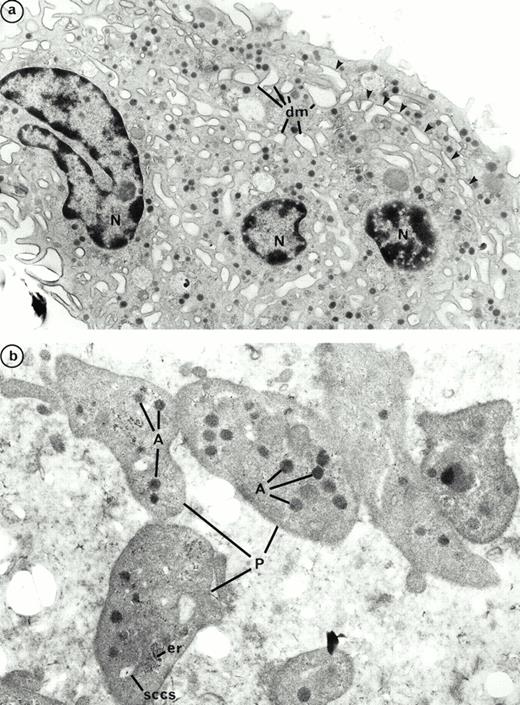

We previously described the ultrastructure of platelet formation by human MKs cultured with PEG-rHuMGDF.29 No substantial differences were observed in the ultrastructure of the platelet-shedding MKs produced in the presence of either PEG-rHuMGDF or the combination of IL-3, SCF, and IL-6. In the two conditions, platelet shedding MKs showed several cytoplasmic expansions which correspond to proplatelets (Figs 9a and10a); constriction zones already individualize distinct platelet fields. In the same way, platelets derived from culture with either PEG-rHuMGDF or the combination of IL-3, IL-6, and SCF were of similar size and exhibited α- and dense granules. Many of these platelets were adherent to MKs; however, they did not exhibit ultrastructural evidence of activation (Figs 9b and 10b). By fluorescent labeling, circumferential microtubule coils and actin filaments were observed with an antitubulin MoAb and phalloidin in the vast majority of the culture-derived platelets (data not shown).

Ultrastructure of platelet shedding MKs and platelets obtained in the presence of PEG-rHuMGDF from CD34+CD41+ cells. (a) A mature MK presenting signs of platelet formation. This MK displays dilatation of the demarcation membranes (dm) located at the periphery. They individualize a zone of cytoplasm (arrows) which will form a future proplatelet (N, nucleus). (b) Platelet-sized-fragments (P) exhibit the usual cytoplasmic organelles: α granules (A), smooth connected canalicular system (sccs), and endoplasmic reticulum (er).